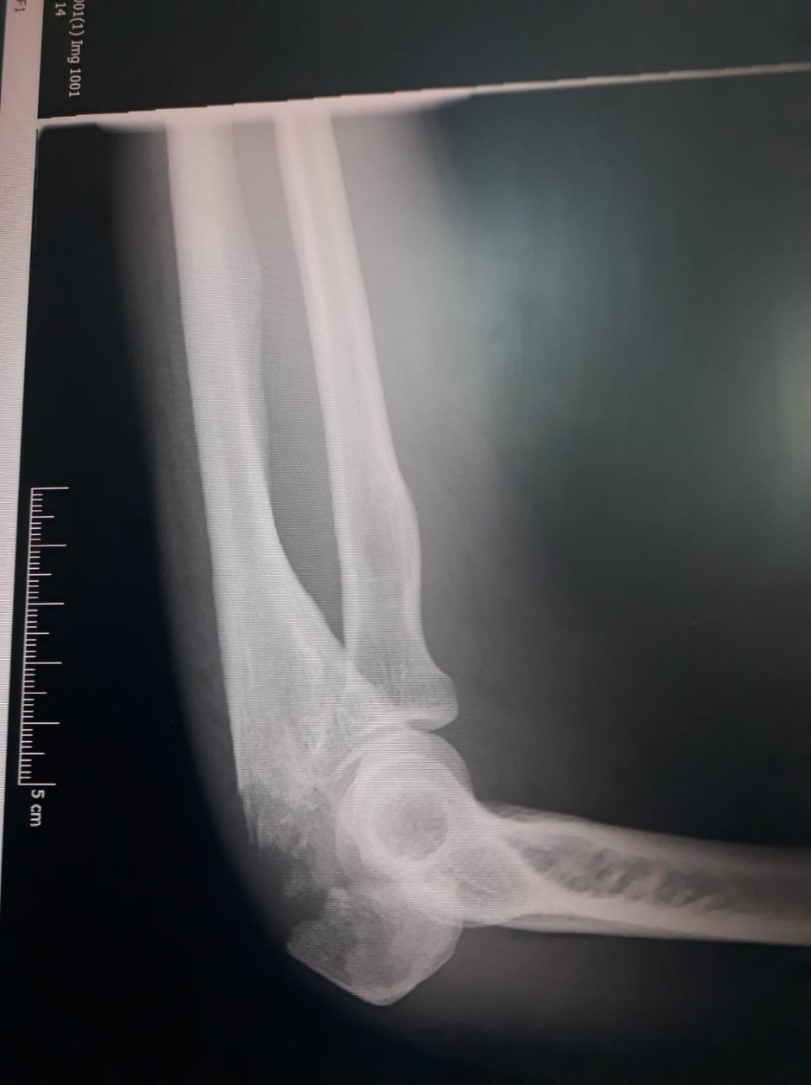

So they plastered my armElbow x-ray To keep it from harm Put a splint on my hand As thumb movement was banned

But for my arm, its fate They’d use a metal plate It would always stay there So metal scanners beware